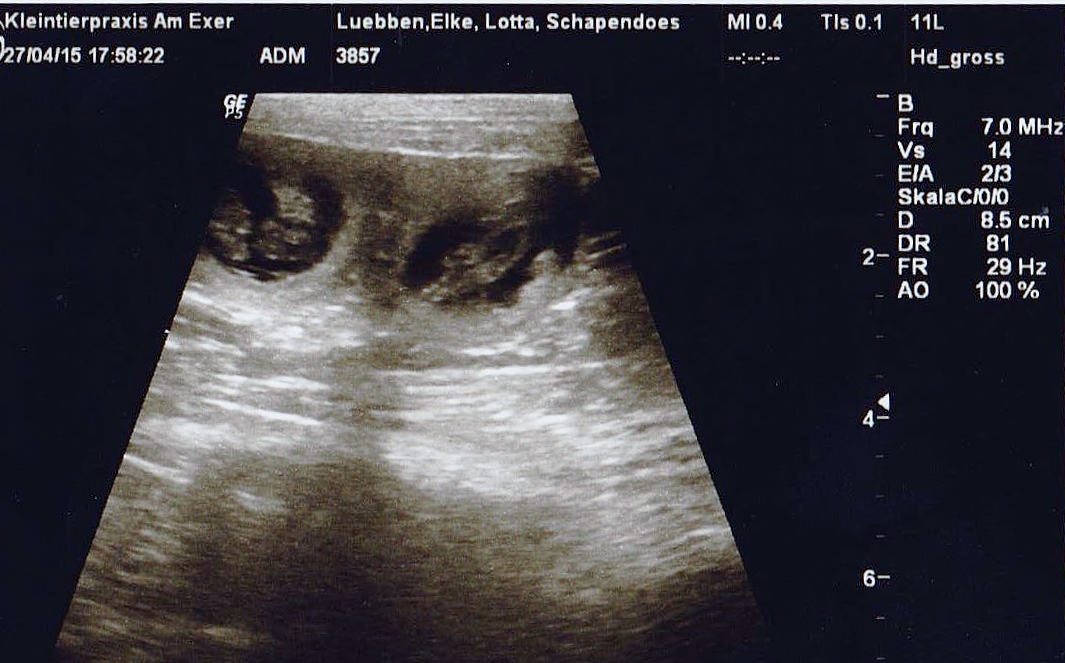

zwei von ????27.04.2015 (28.Tag)... Nun haben wir es schwarz auf weiß..... der Ultraschall zeigt, das Treffen von Lotta und Tjano hat Früchte getragen;))) Lotta hat es uns eigentlich auch schon ziemlich deutlich die letzte Zeit angezeigt... ihre Anhänglichkeit, Ruhe und ihr eindeutig "schwangerer Blick" seit mindestens zwei Wochen ließen es schon erahnen. Aber man weiß ja nie... Neue Formen hat dieses Mal hingegen ihre Fresslust angenommen. Da sie bereits jetzt eindeutig meint, sie bekomme mindestens zwei Tagesportionen pro Tag zuwenig, mussten wir inzwischen hohe Barrikaden zu Nachbars Garten bauen. Durch diesen entwischte sie die letzte Zeit immer häufiger und ziemlich zielstrebig .... durch die offene Terrassentür in des Nachbars Küche... DAS hat sie bisher noch NIE gemacht;))) Ansonsten geht es ihr mal wieder prächtig.